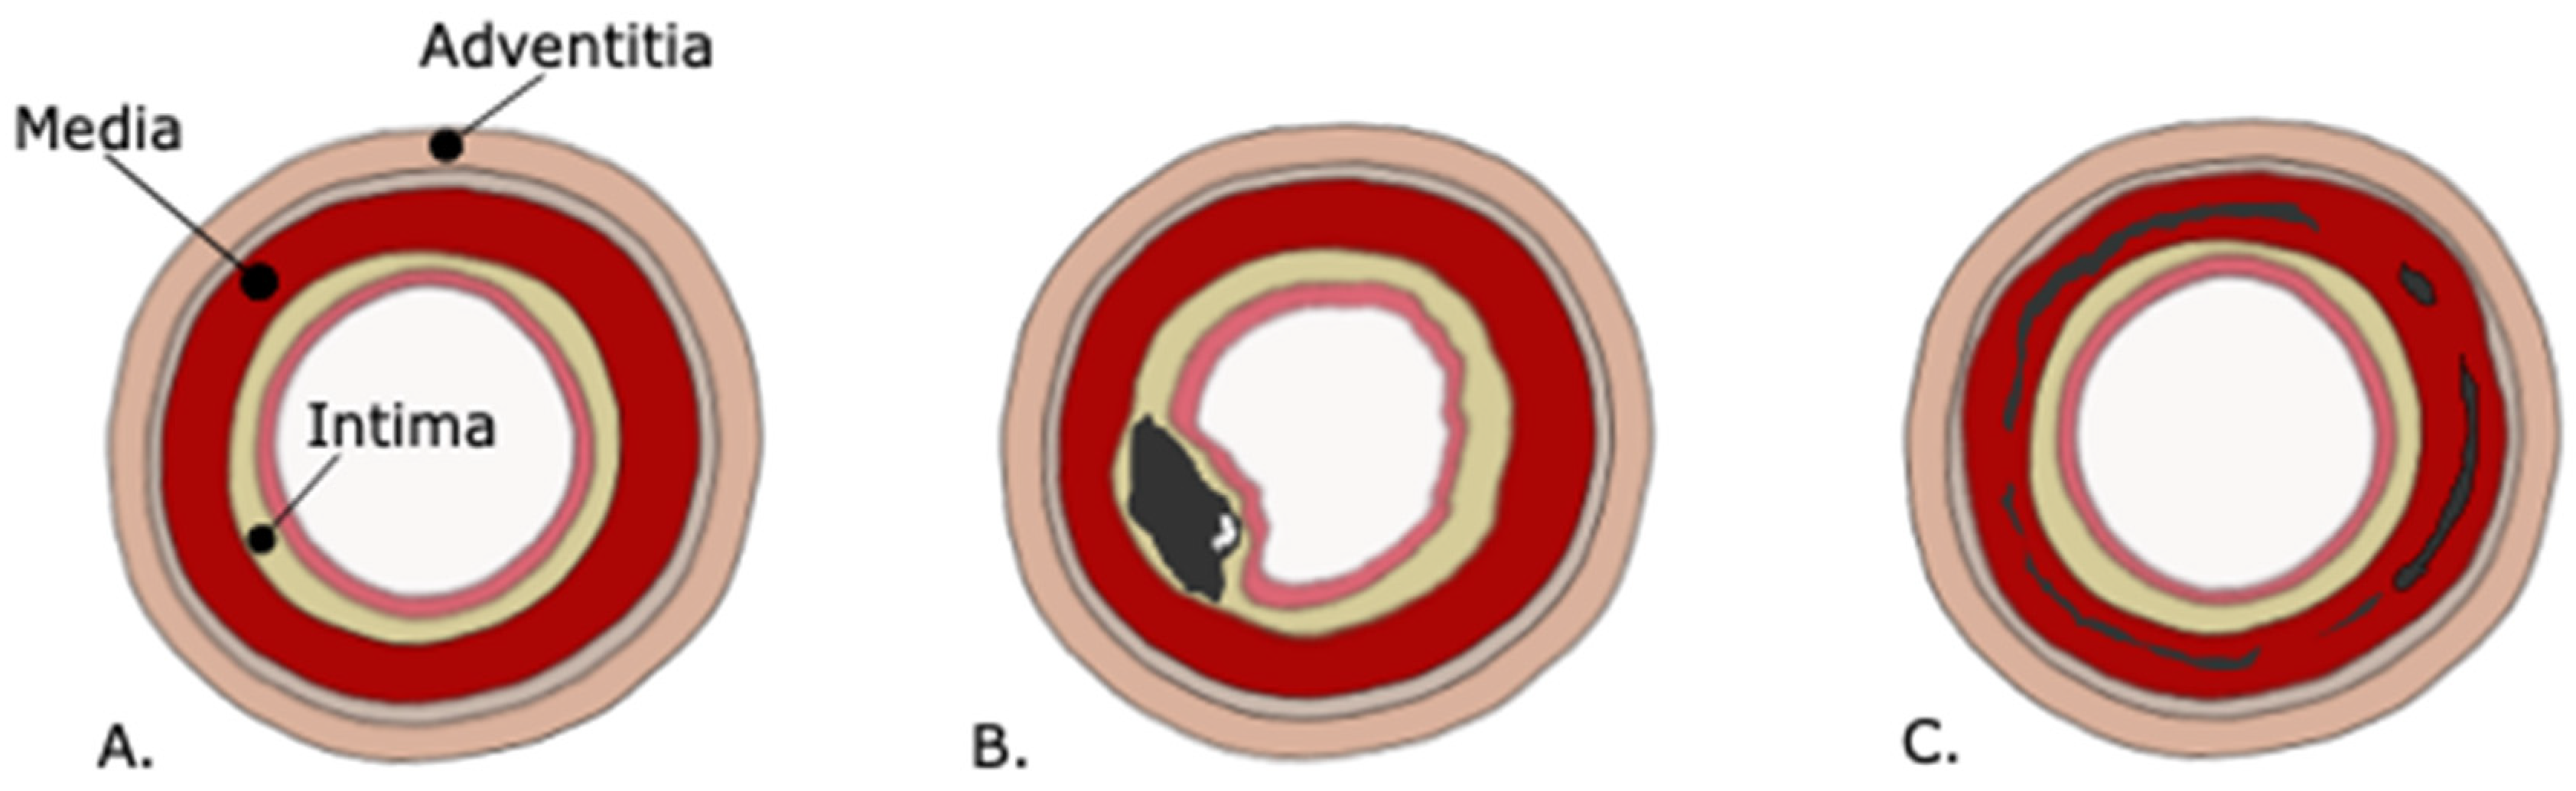

Figure 1.

(A) Wall layers in a normal artery from inside to outside: endothelium, tunica intima (internal elastic membrane and fibrocollagenous tissue), tunica media (smooth muscle), tunica adventitia (external elastic lamina and fibrocollagenous tissue). (B) Calcifications in the intimal wall: thick and non-annular. (C) calcifications in the medial wall and in the internal elastic lamina: thin and annular.